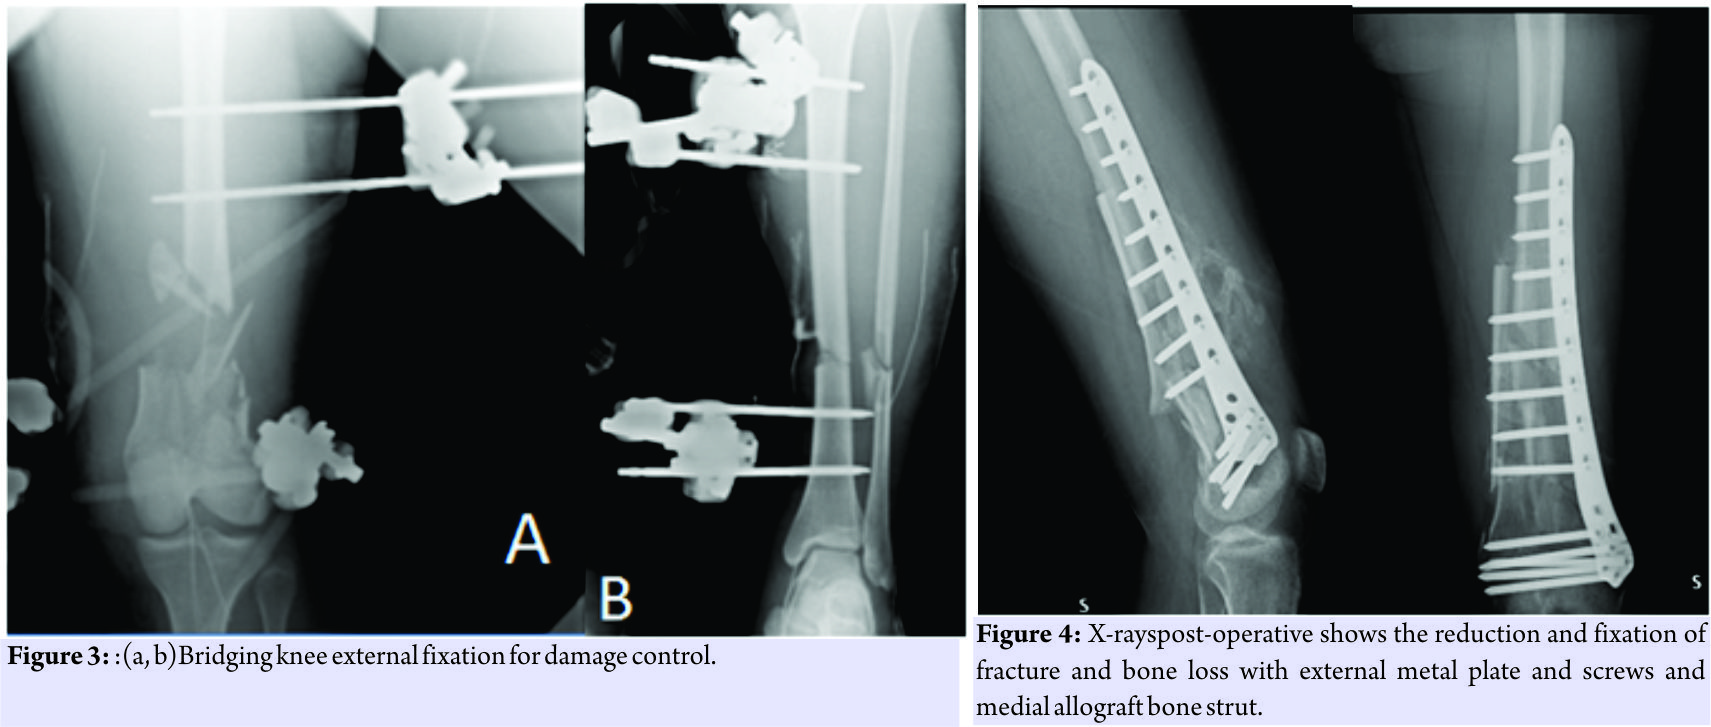

At 4:30 am, a 23-year-old patient arrived at our drug enforcement administration, after a high kinetic energy car accident (car against the wall) in orotracheal intubation with a Glasgow coma scale (GCS) of 11/15, mangled extremity severity score 4 points for the femur, and 3 points for the leg, and an injury severity score of 24 points:oderate concussion, moderate splenic ulcerations, supra-intercondylar fracture of the femur (3.3-C1 according to AO) left exposed Gustilo Anderson (GA) IIIB and bone loss of the metaphyseal area >50% and shaft fracture(Fig.1 and 2) with a third fragment (4.2-B2 according to AO) exposed GA 3B(Fig.1). The patient was treated in emergency with a bridge femorotibial external fixator after extensive cleaning and debridement of open fractures(Fig.3a and b). After stabilization, the wounds were covered with iodine-impregnated incision drape (Ioban). During the damage control’s operations, a fragment of 8 cm × 3 cm × 4cm of bone substance corticospongiosa was found in the left sock. The fragment was immersed in a solution of cefuroxime, gentamicin, and metronidazole and maintained at a temperature of −3°C until 2h before the intervention because it was irradiated with a dose of 25kGy. The 4days, we removed the antibiotated chains and the Ioban cover which were replaced with vacuum therapy. The patient never had fever over 38°Cduring his 10 days in intensive care and in the ward. The delayed risk of tibial consolidation was equal to 8 of 10 according to A.R.R.C.O. As regards the femur, the risk of non-union of the fracture of the femur of 51 points according to the non-union scoring system(N.U.S.S).

The patient was treated in emergency with a bridge femorotibial external fixator after extensive cleaning and debridement of open fractures(Fig.3a and b). After stabilization, the wounds were covered with iodine-impregnated incision drape (Ioban). During the damage control’s operations, a fragment of 8 cm × 3 cm × 4cm of bone substance corticospongiosa was found in the left sock. The fragment was immersed in a solution of cefuroxime, gentamicin, and metronidazole and maintained at a temperature of −3°C until 2h before the intervention because it was irradiated with a dose of 25kGy. The 4days, we removed the antibiotated chains and the Ioban cover which were replaced with vacuum therapy. The patient never had fever over 38°Cduring his 10 days in intensive care and in the ward. The delayed risk of tibial consolidation was equal to 8 of 10 according to A.R.R.C.O. As regards the femur, the risk of non-union of the fracture of the femur of 51 points according to the non-union scoring system(N.U.S.S). The patient was not treated surgically for the fissure of the spleen, and the resolution of the neurological picture took place after 6 days. The patient was submitted to a specific antibiotic therapy according to the protocol for the open fractures and was monitored with clinical and laboratory examinations. The 21stday post-trauma, without any clinical or laboratory signs, the patient was operated on with a less invasive stabilization system plate and screws, cortical and cancellous bone grafting allogeneic bank, and autologous stem cells taken from the iliac crest, PRP rich in leukocytes and replanting of native bone. The surgical access chosen was the lateral subvastus to preserve the perforating arteries(Fig.4). The patient was monitored with 15 days clinical follow-up, laboratory, and radiological at 1 month, 2 months, 3 months, 6 months, 12 months, 18 months, 24 months, 36 months, and 48 months. The indices used to evaluate the outcomes of this intervention were the knee injury and osteoarthritis outcome score (KOOS), the related union scorefemur (R.U.S.F.) for the femoral bone healing, and the score radiographic union score for tibial fractures (R.U.S.T.). For bone consolidation of shank, the short form 12 health survey (SF-12) for the quality of life, and the number of complications and re-operations. The patient in the immediate post-operative made active and passive mobilization of the knee until the 3rdmonth, reaching a flexion of 90°. The patient was subjected to the intervention of removal of the external fixator and intramedullary nailing of the tibia 3 months after the first surgery(Fig. 5).

The floating knee is unfortunately always associated with more internal injuries that make it difficult to provide a total care early on [6]. Furthermore, in our case, we had a double IIIB exposure which is very rare in floating knee IIB according to Fraser. Looking at the ISS score and the GCS, we must put a damage control in place [7], before the stabilization of both bone fragments, it is essential to carry out a careful debridement and thorough washing with a physical examination of the exposition. As reported by Veith, to have a chance of a good outcome, and also to save the patient’s life and reduce perioperative complications, it is necessary to optimally stabilize both segments. In fact, our choice fell on the external fixation, putting the knee bridge in bending at 20°. To maintain the highest possible sterility and preserve the sites of exposure by superinfection of resistant super bacteria residing in TI, we have isolated the bone exposure with a steri-strip with betadine [8] waiting to activate the vacuum-assisted closure (VAC) therapy at the moment not yet available at our structure. As shown by Grubor et al. [9], the use of VAC therapy in open fracture IIIB Cierny and Mader IIIB osteomyelitis drastically reduces the risk of septic shock and limb amputation. In the literature, there are not many studies, but a few case reports show the opportunity to replant large fragments of bone devascularized, however, to make this replanting on final osteosynthesis you need to make careful cleaning and debridement. The bone fragment was sent to the bone bank for a proper preservation and thawed 2 days before, to be subjected to a treatment for decantation in antibiotics and irradiation with ionizing rays to avoid the formation of bacterial biofilms on the surface of the implant. The treatment by decantation in the three antibiotics was fundamental: Gentamicin for the broad spectrum against g + and g − bacteria, in particular against Escherichiacoli, coliforms, Pseudomonas aeruginosa, and Proteus [10] and for the ability to perform a surfactant function that covers the bone surface and prevents the adhesion of bacterial colonies [11]; cefuroxime, also for the broad spectrum of action and in particular the activities toward all Staphylococci and Streptococci and metronidazole for the activity to all anaerobes as Freeman et al. [12].In the literature, there is no consensus on how to permanently sterilize bone segment to replant, however, Singh et al. [13] showed the high rate of sterilization of tumor cells from soft tissue using the autoclave. However, the use of the autoclave to the high temperatures destroys the osteoinductive capacity and mechanical bone to replant [13]. According to ISO 11137, 2002 to sterilize the bone serve a 25 kGy of ionizing rays, in fact, Aizah et al. [14] showed a success in the replanting of a distal femoral metaphysis (open fracture IIIA GA) in a young man of 14 years after sterilization by gamma irradiation of the entire fragment. Finding ourselves in front of a massive bone loss >50% of the distal metaphysis of the femur and a N.U.S.S score of 51, we had to resort to diamond concept, being comparable to a Grade 3 N.U.S.S, or rather compromission of both biological and mechanical segments. We decided, even in the absence of inflammatory or septic manifestations, to wait 21 days for the final intervention, as a soft callus was formed which is comparable to a primordial biological room. At the same time, the necessary time for the formation of our biological room with respect to the distal femur had relapsed; we had to choose among three possible treatments: The method of pseudomembrane of massequet, the double opposed plate of metal according Ruedi, and the organic metal solution according to the Bologna’s school. The choice of the method was carried out in the surgery room, after the subvastus lateral access for the preservation of the perforating [15], and therefore, the respect of the biology of the lateral compartment. It was decided to opt for the organic metal solution, as from the experience of periprosthetic femoral fractures, the contrast between a splint bone and a metal plate increases the mechanical strength of the femur 2250 N and is the best biological solution, considering that the splint has a mechanical filler as well as a stimulus for the bone’s growing [16]. Our technique has been put in place respecting the algorithm devised by Calori et al. [17], with the only change the PRP and mesenchymal cells instead of Bone morphogenetic protein-7, for exploiting the totipotent capacity of leukocytes to turn into osteoblasts [17]. Having a ligament stability from both the collaterals and cruciates, and because we did not have a fibrous retraction, nor a knee pseudoankylosis since the early moments of the intervention, we made a cautious passive knee kinesis with a progressive increase of joint range of motion during the post-operative days. The external fixator leg during surgery had been overhauled by placing compression fragments to heal the fracture of tibia with that kind of synthesis. We scored ARCO and could see both direct and indirect radiological signs of modest bone callus, 3 months after, the tibia had been repaired with plate and screws, to increase the partial load bearing ability, the patient had been able to progress to total load bearing; there were also direct and indirect bone regeneration and strengthening of the femur that allowed the patient to walk with aids. Although trivial, we were able to ascertain that the mood of the patient was directly related to the ability to walk that was gradually acquired [18]. The clinical and radiographic results in the case reported are certainly encouraging, demonstrating that at least part of the “biological push” provided by the use of stem cells is capable of increasing the potential of synthesis techniques, however, we should not underestimate the opportunity to attack the biological chamber through the soft tissue and the possible role of the post head trauma somatostatin secretion that may assist the regenerative potential of stem cells. Furthermore, the placement of a splint to the medial cortical bone level opposite to the plaque leads to an increase of the resistance of the femoral medial wall to almost 2250 Newton giving the femoral shaft undisputed biomechanical advantages. These results encourage a continuation of the experience and a comparison with the literature for results that are uniform for each one.